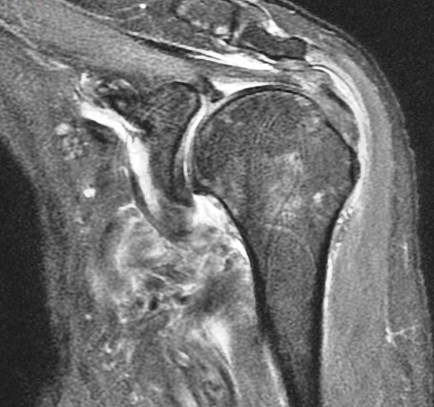

75 y/o s/p dislocation

Dislocation pathology is typically different in older patients than younger patients. The great majority of first time dislocators under the age of 40 suffer a bankart lesion (avulsion of the labral ligamentous complex on the glenoid side). Older folks often suffer a rotator cuff tear including the supraspinatus or subscapularis (or both). This patient had an SST tear but in addition also has a HAGL lesion (humeral avulsion of the glenohumeral (IGHL) ligament). She also has subscapularis partial tearing associated with a near complete dislocation of the biceps (findings that I think were preexisting). Reference article.

HAGL lesion and rotator cuff tears